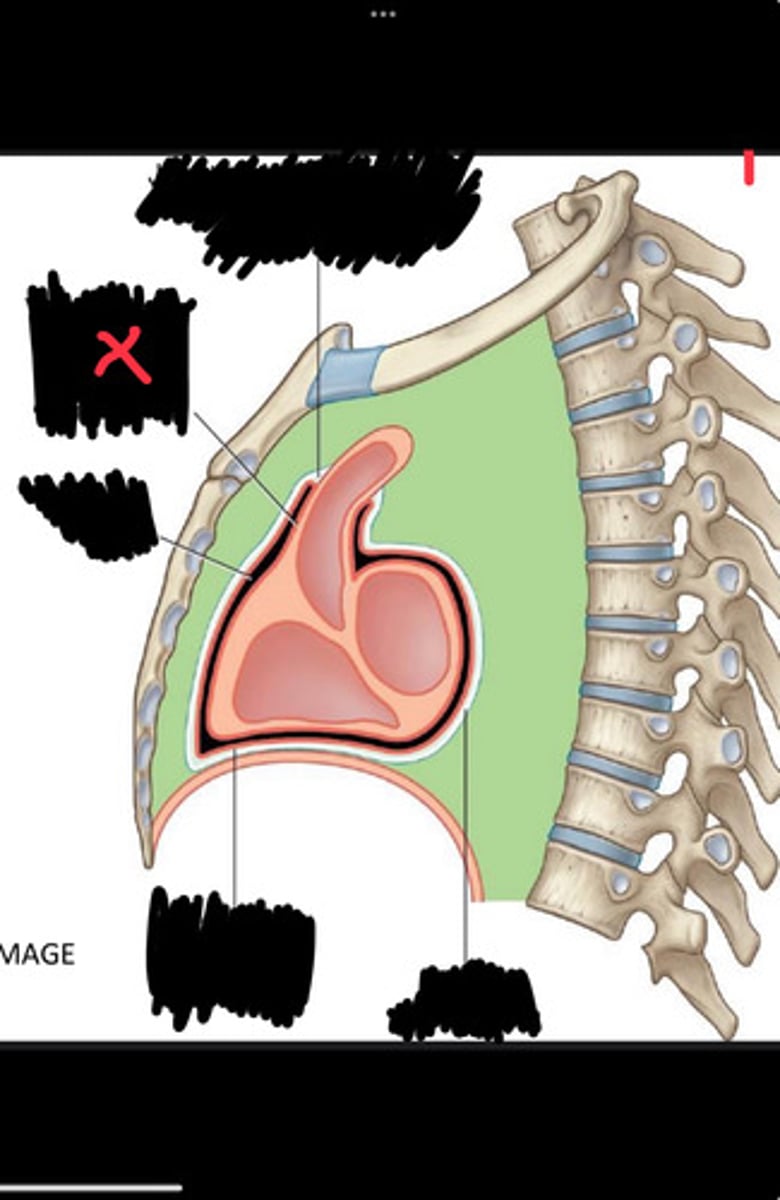

Fibrous pericardium

Parietal layer of serous pericardium

Pericardial cavity

Visceral layer of serous pericardium

Junction between fibrous pericardium and adventitia

Heart

Thoracic aorta

Rib 1